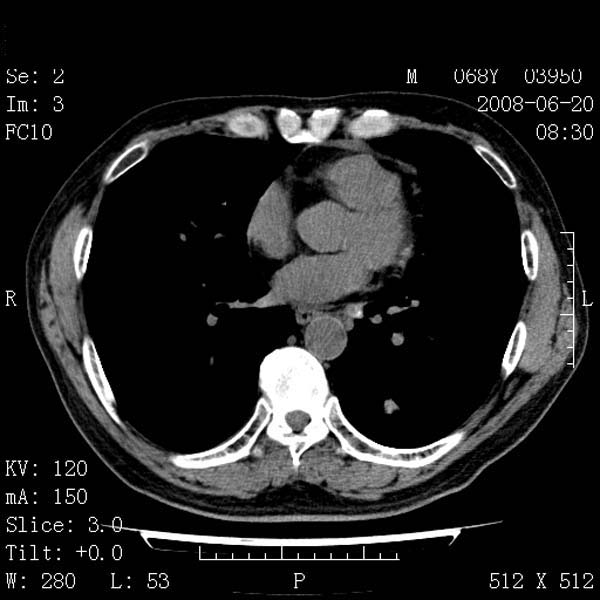

以下是引用守望可可西里在2008-6-24 1:11:00的发言:[br][br] 考虑为周围型肺癌:[br] 1.分叶结节,形态极不规则,蟹足样伸展的恶性浸润特征比较明确。[br] 2.磨玻璃影中由多个更高密度小结节聚集呈梅花瓣样。[br] 3.局部胸膜凹陷征比较明确。[br][br] 另:纵隔胸膜明显增厚、粘连。

以下是引用zjzjr在2008-6-24 11:19:00的发言:[br]支持左下肺周围型肺癌伴右肺转移,纵隔淋巴结转移,心包积液.

以下是引用zhangling在2008-6-24 14:56:00的发言:[br]我们科室意见报告为[br][br]1考虑左下肺周围型肺癌[br]2右肺小结节考虑转移瘤,纵隔淋巴结转移[br]3心包积液. [br] 各位老师分析的相当好 谢意[br]